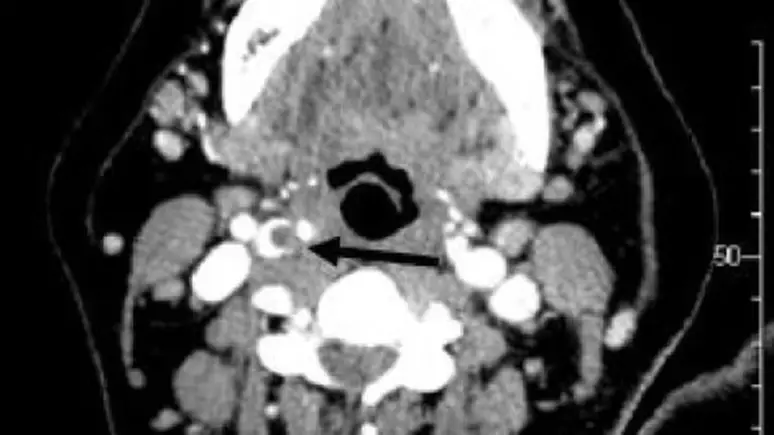

Neurologista descreve essa lesão como uma dissecção da artéria carótida

A questão que surge é: como um gesto aparentemente inofensivo pode evoluir para um problema tão grave? Especialistas explicam que a pressão aplicada durante um chupão pode lesionar a artéria carótida, responsável por transportar sangue do coração para o cérebro. O neurologista Felipe Aydar Sandoval, do Hospital Sírio-Libanês, descreve essa lesão como uma dissecção da artéria carótida, que é uma ruptura na parede da artéria, podendo resultar em sangramento e redução do fluxo sanguíneo cerebral, informou ao G1.